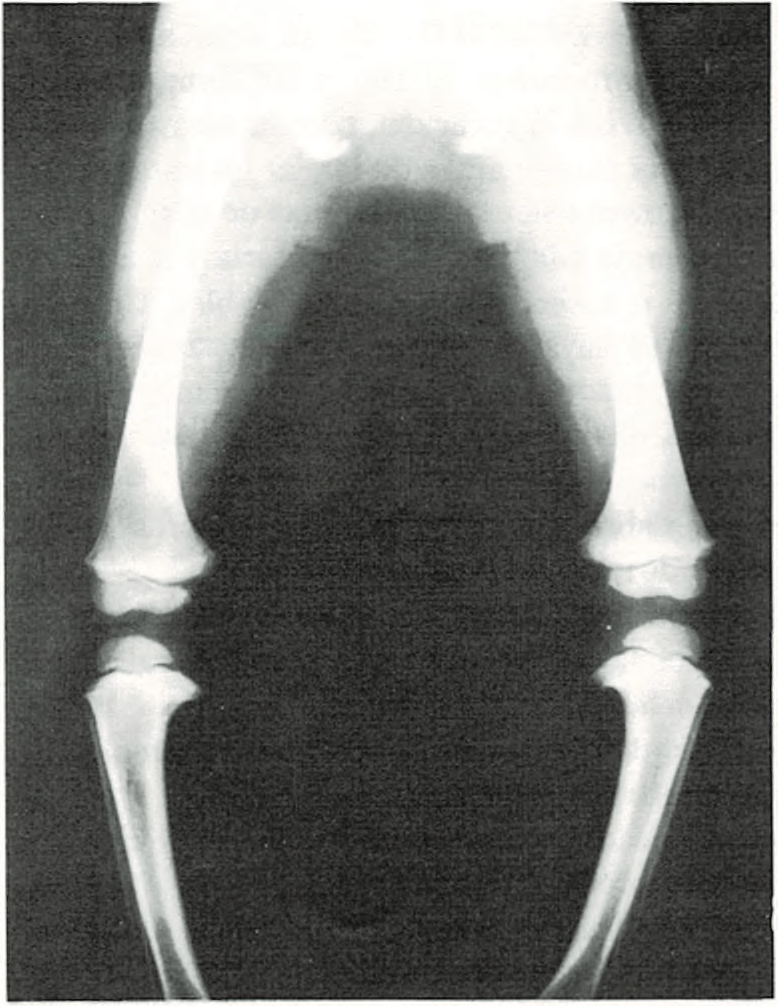

Pie Zambo

La deformación denominada del “pie zambo” es la más común con la que

Se comenzó tratamiento correctivo antes del año de edad.

puede nacer un niño. Generalmente el pie zambo, llamado también pie varo, está torcido hacia dentro y hacia abajo, lo que produce una deformación típica en las extremidades inferiores. Se presenta en determinadas familias y es más común en los niños que en las niñas. Ocurre una vez entre 1.000 nacimientos.

Se puede presentar en uno o en ambos pies y la gravedad oscila entre las formas leves hasta las más importantes que necesitan un cuidado muy especial. Este último caso será el cirujano ortopedista (especialista en alteraciones de los huesos) el que lo dirija. El tratamiento incluye masajes, zapatos especiales, tablillas correctoras o yesos y, en algunos casos, una operación. Los mejores resultados se obtienen cuando se comienza el tratamiento preferentemente antes de que el niño tenga un año de edad. Si se retrasa, puede ser más difícil la corrección de la deformidad y los resultados no tan buenos.